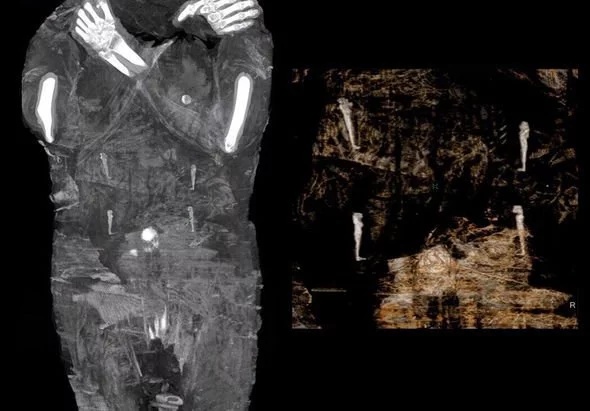

At the time, X-ray scans and 3D reconstruction of the embalmed body did not reveal a key anatomical detail typically associated with male remains.

Instead, subsequent scans revealed what appeared to be a tiny foot within the woman’s abdominal area.

She told the Polish Press Agency (PAP): “We took one last look at the X-ray images and saw in the woman’s abdomen something familiar to parents — a small foot.”

As for the woman’s unborn child, limited details are available. Researchers determined the baby was positioned in a natural prenatal posture, although its sex has not been identified.

Although rare, this mummy retained preserved soft tissue, allowing researchers to detect minimal biological traces within the remains.

Researchers noted that the woman’s uterus appeared unusually rigid, which could support this idea.